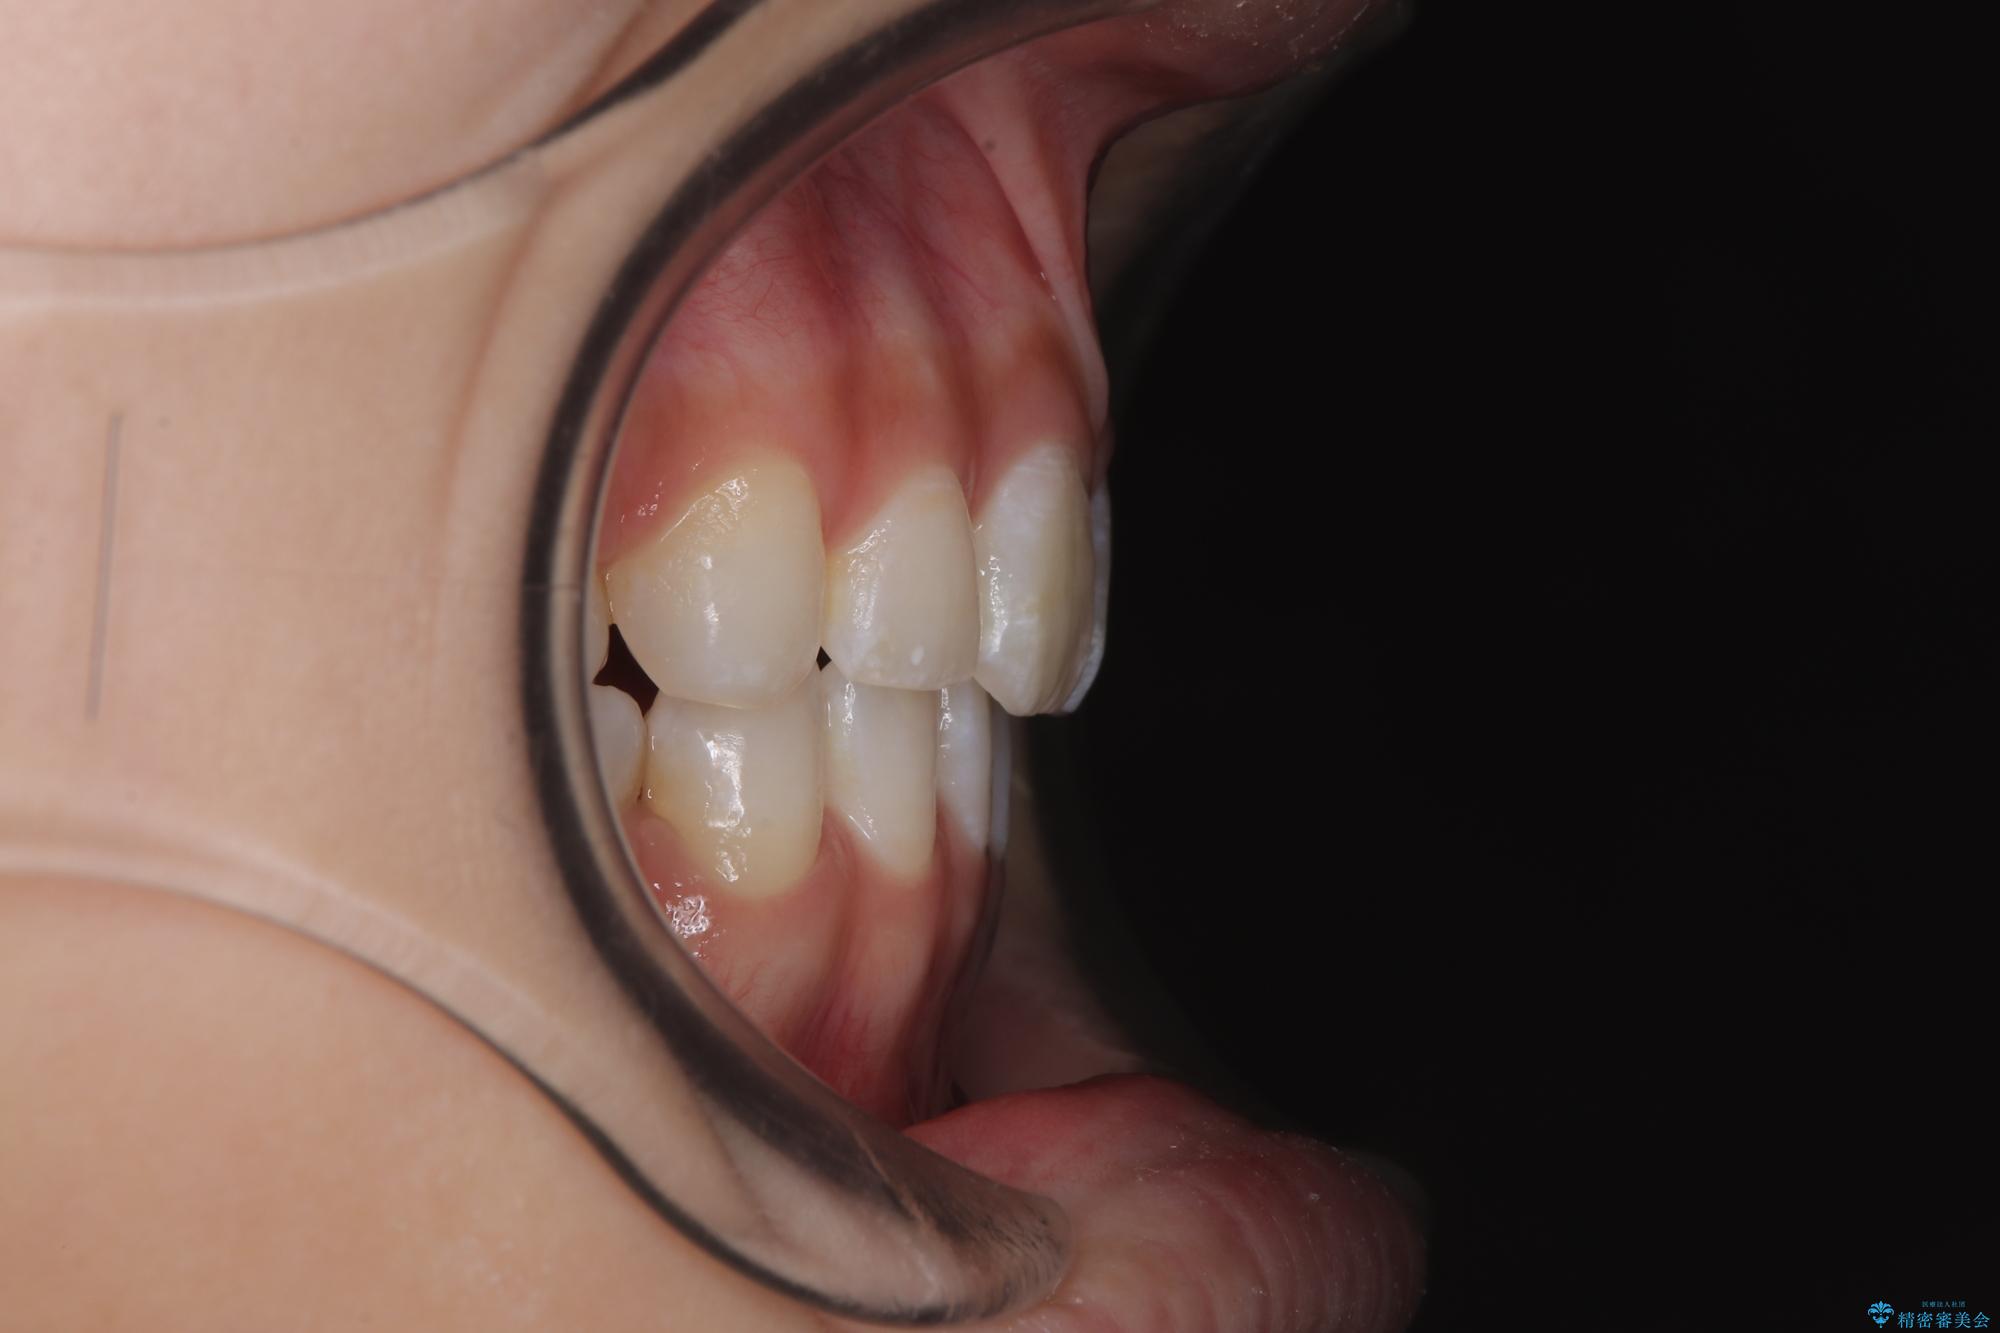

斜め前に飛び出した前歯 抜歯矯正で素敵な横顔に

- 口を閉じたときに飛び出してしまう上顎前歯を気にして来院された患者様です。

下唇に前歯が当たって跡が残ってしまう状態でしたが、スッキリとした口元に仕上げることができました。